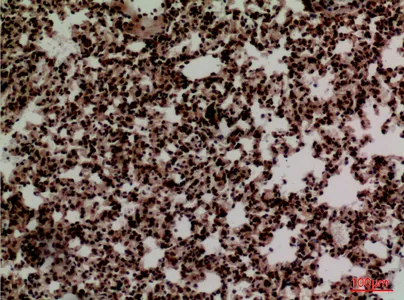

HDC Rabbit Polyclonal Antibody

Cat: APRab11956